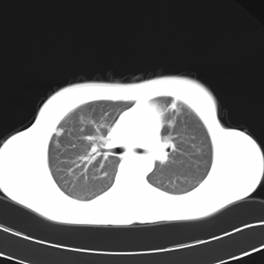

影像学检查:

CT左侧乳腺癌保乳治疗术后,双肺发转移瘤;

两个月后患者到医院复查CT发现,双肺发转移瘤明显实现了瘤体萎缩。